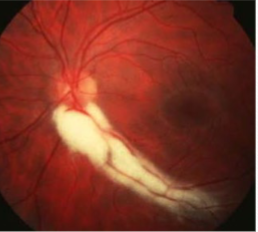

corkscrew prepapillary vascular loop

congenital

appearance:

aberrant development of retinal vasculature system (arterial usually but can be venous)

unilateral vessel loop arising from disc & returning to disc

extends up to 1/3 into vitreous cavity

may be partially enclosed w/ glial tissue

concurrent cilioretinal arteries in 75% of cases

complications:

must r/o acquired loops

rare BRAO/CRAO, TMB, recurrent vitreous hemorrhage, subretinal hemorrhage